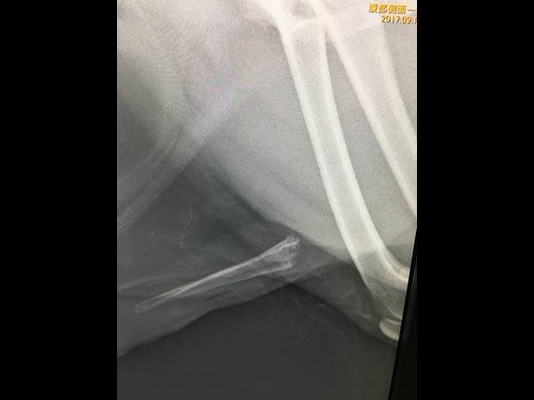

尿道結石がスタックされていて膀胱内に押し込むこともできない。押し込んでも何度も落ちてきて尿道に詰まってしまうことがある。

尖っている結石が粘膜に刺さっていると押し込むことも不可能になります。

他院からの紹介:結石が詰まってチョロチョロしか尿が でずカテーテルも通らない。

結石破砕を依頼された。左が破砕前、陰茎骨に結石が詰まっている。

右は破砕後。破砕が可能だったので尿道切開をせずに2時間後に帰宅した。